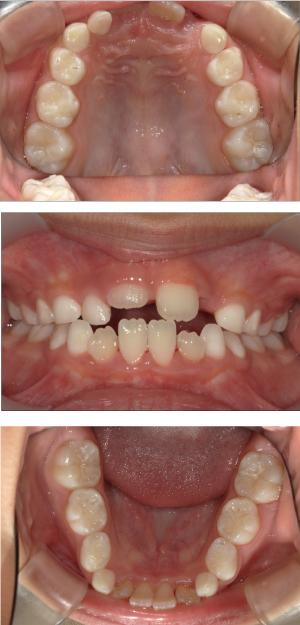

バイオブロック矯正(顎顔面口腔育成治療)

矯正治療は大人になって始めるよりも子どもの頃から始めた方が確実に良い結果をもたらします。成長が盛んな子供の時期に、顎や顔の成長を利用しながら治療ができる大きなメリットがあるからです。当院では、非抜歯矯正を推奨しておりバイオブロック矯正を取り入れています。

バイオブロック矯正の考え方は歯並びが悪くなる原因にアプローチする治療法になります。

舌の位置や口呼吸から乱れてしまった下顎の後退を正し、顎顔面が本来あるべき位置へと誘導させていく治療です。

- 歯並びの改善

治療開始年齢

6.7歳以降~10歳前後まで

(歯の生え変わりスピードによって個人差はございます)